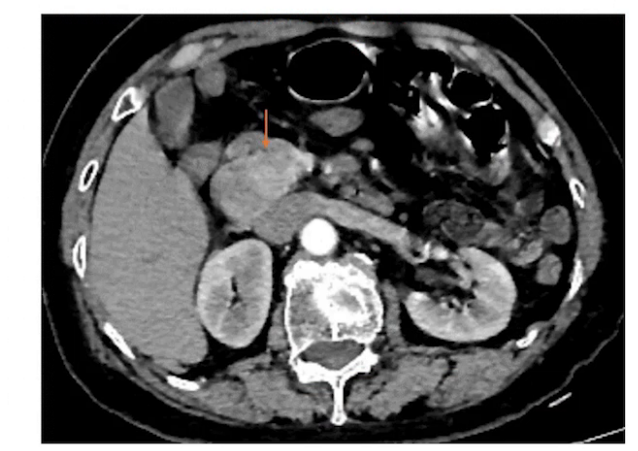

腹部CT:十二指肠降部占位,考虑神经内分泌瘤或间质瘤可能,肝脏多发囊肿,胆囊胆汁淤积,双肾多发小囊肿,双肺下叶斑片影。